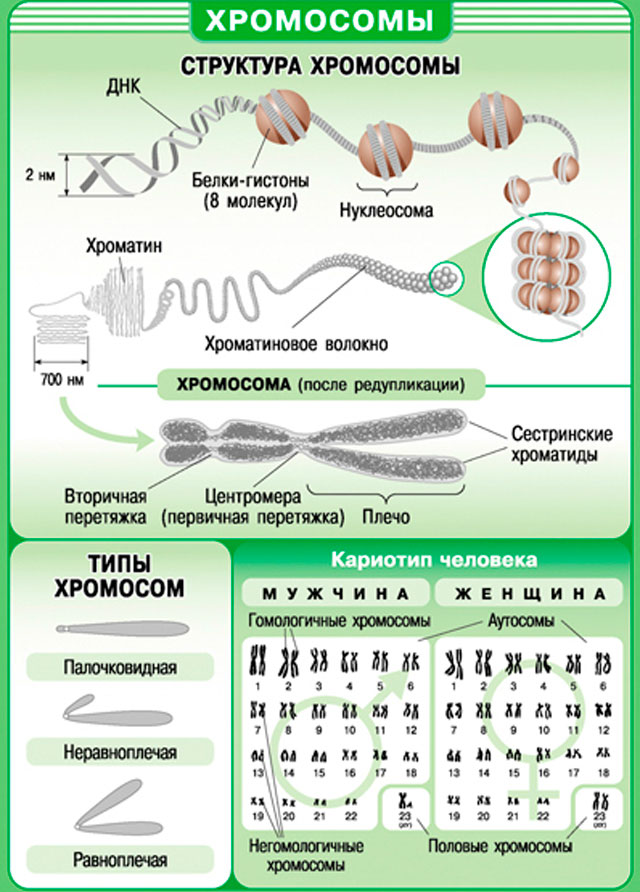

Біологія — точна наука. Дві X — хромосоми- це дівчинка, а XY – хлопчик. Але як вони утворюються. Варто пам’ятати, що для зачаття необхідні гени як батька, так і матері, без них ні про яке зародку не може бути мови. Але справа в тому, що жіноча яйцеклітина завжди є носієм X хромосоми, оскільки жіночий організм Y хромосоми просто не містить.

А ось сперматозоїд може нести як X, так і Y хромосому. Стать дитини, відповідно, залежить від батька, а не матері.